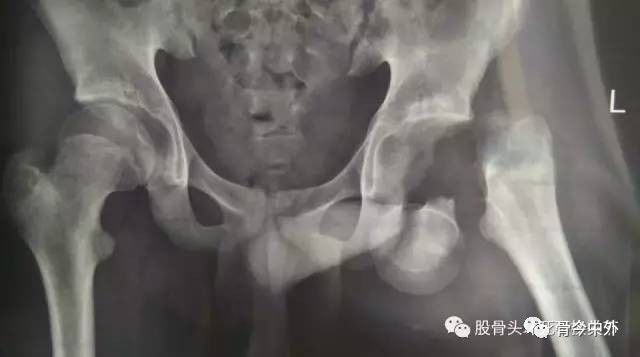

图2?股骨颈garden 4型,坏死率极高

图3?女,19岁,股骨颈骨折10余年,继发股骨头坏死、股骨颈短缩畸形,下一步治疗面临艰难的选择